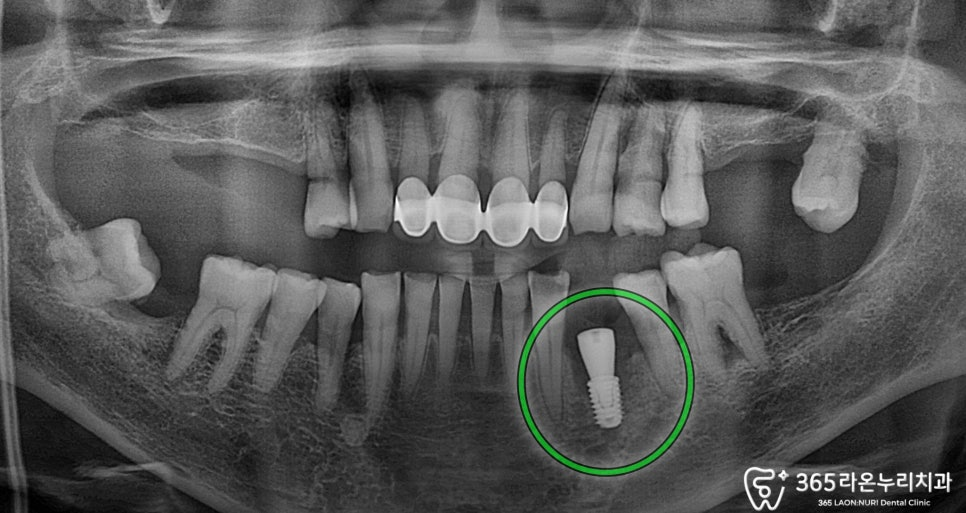

뼈이식 후 바로 식립을 진행 후,

서정리역 치과 에서

파노라마 엑스레이를 보면

정확한 위치에 식립한 모습을 볼 수 있습니다.